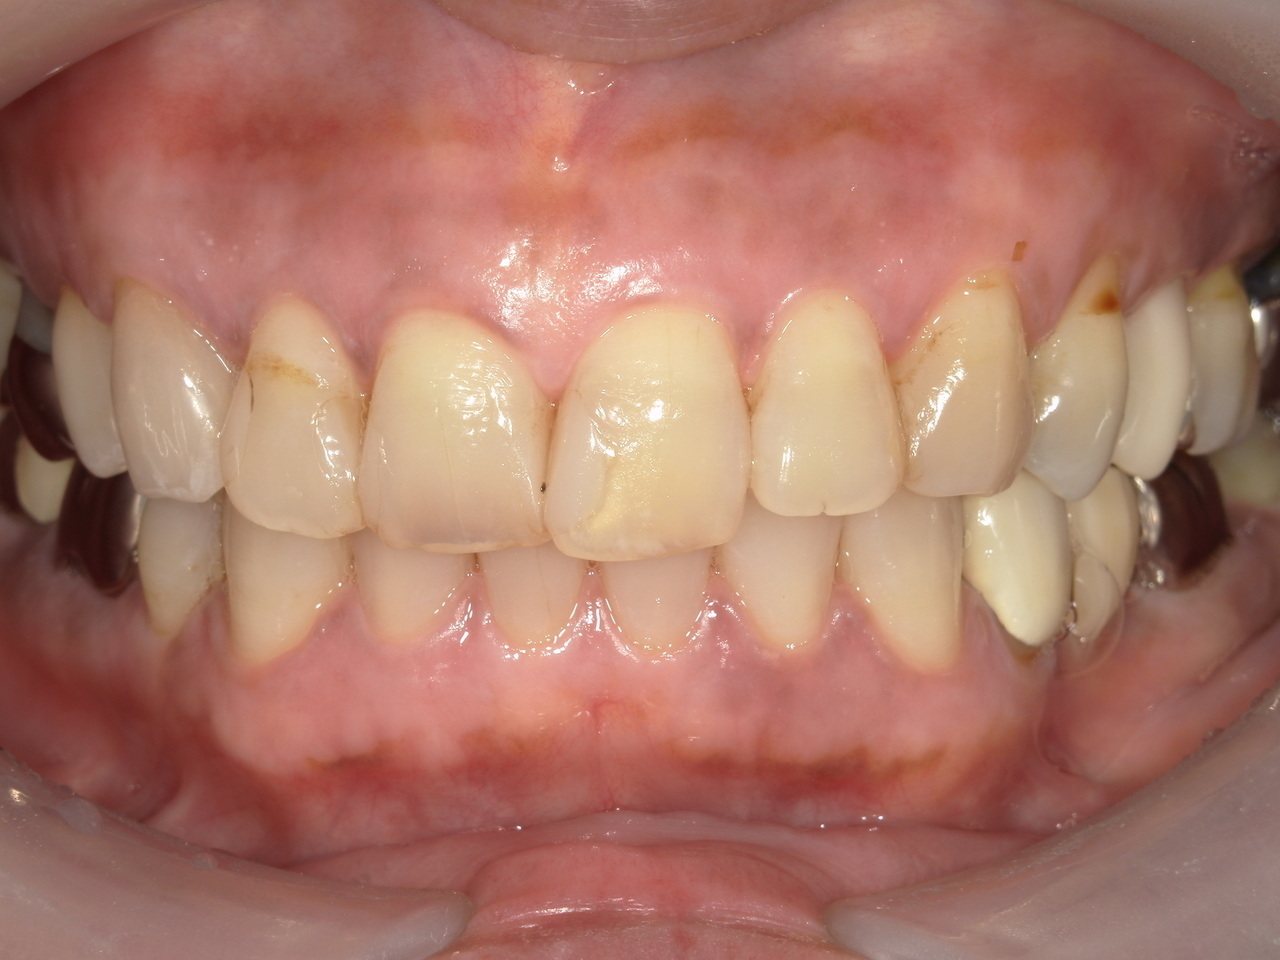

10日後白い薄皮が剥がれて、

ピンク色の歯茎に変わります。